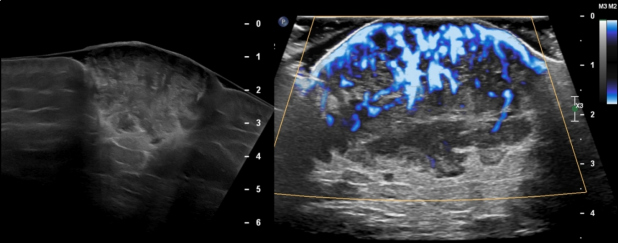

Mujer de 49 años con antecedente de leucemia de células pilosas (tricoleucemia) de riesgo bajo, en remisión completa. En septiembre 2020 presentó aumento de volumen en región supero-interna del glúteo derecho; ante la sospecha de una infección de tejidos blandos recibió antibióticos, sin mejoría. El mismo mes fue valorada en nuestra institución por la presencia de una neoformación cutánea dolorosa en glúteo derecho. Se realizó ecografía de la lesión dérmica (fig.1) y una tomografía de abdomen y pelvis en fase venosa, donde se observó una lesión sólida de 45 x 24 x 41 mm, con márgenes bien definidos y lobulados. Además se detectaron adenopatías ilíacas comunes, en cadena ilíaca interna derecha y en región inguinal homolateral, de entre 15 y 51 mm. Referida la paciente al servicio de Dermatología, la lesión fue descrita como una neoformación de aspecto nodular, cupuliforme, de 4 x 5 cm de diámetro, superficie lisa y violácea, sólida, a la dermatoscopía con patrón reticular y áreas rosas y blancas, sin estructura (fig. 2). Posteriormente se realizó biopsia por huso de la lesión glútea, con reporte de patología de carcinoma invasor de células de Merkel con invasión a dermis profunda (CK-, CK20+, Cromogranina +, Sinaptofisina -, Ki67 80%, CD56+, CD117+); además se tomó una biopsia excisional del conglomerado ganglionar inguinal, que confirmó la presencia de metástasis. Como parte de su estadiaje, en enero de 2021 se realizó un estudio PET/CT con 18F-FDG que documentó incremento focal del metabolismo en la lesión, así como adenopatías hipermetabólicas cervicales, retroperitoneales, ilíacas bilaterales e inguinales derechas. Debido a un sangrado no controlado del tumor, se procedió a la resección de la lesión glútea y colgajo de muslo posterior sin complicaciones, reportando márgenes quirúrgicos negativos. Al tratarse de una enfermedad metastásica, se administró quimioterapia a base de etopósido y cisplatino, en 5 ciclos desde marzo a junio y se realizó nuevo PET/CT con 18F-FDG para evaluar respuesta a tratamiento. Por presentar oligo-progresión ganglionar (adenopatía pericecal hipermetabólica), recibió radioterapia corporal estereotáctica (SBRT) 45Gy en 6 sesiones desde junio a julio de 2021. En agosto se realizó un nuevo PET/CT donde se observó desaparición de la adenopatía antes mencionada y una nueva lesión nodular de bordes lobulados en región glútea derecha de 36 x 32 mm con SUV máximo de 15,6. La fig. 4 muestra el MIP de los 3 estudios PET/CT: inicial, post-resección + quimioterapia y post-radioterapia. La paciente continuó su tratamiento experimentando respuesta completa aunque más tarde se comprobó recaída local y ganglionar, todo lo cual fue documentado mediante PET/CT, no incluído en esta publicación.